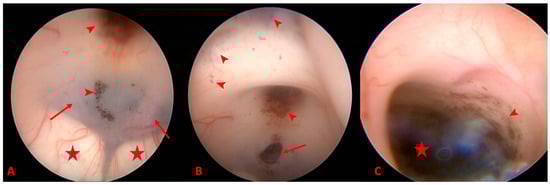

2. Detailed Case Description

3.2.2. MRI